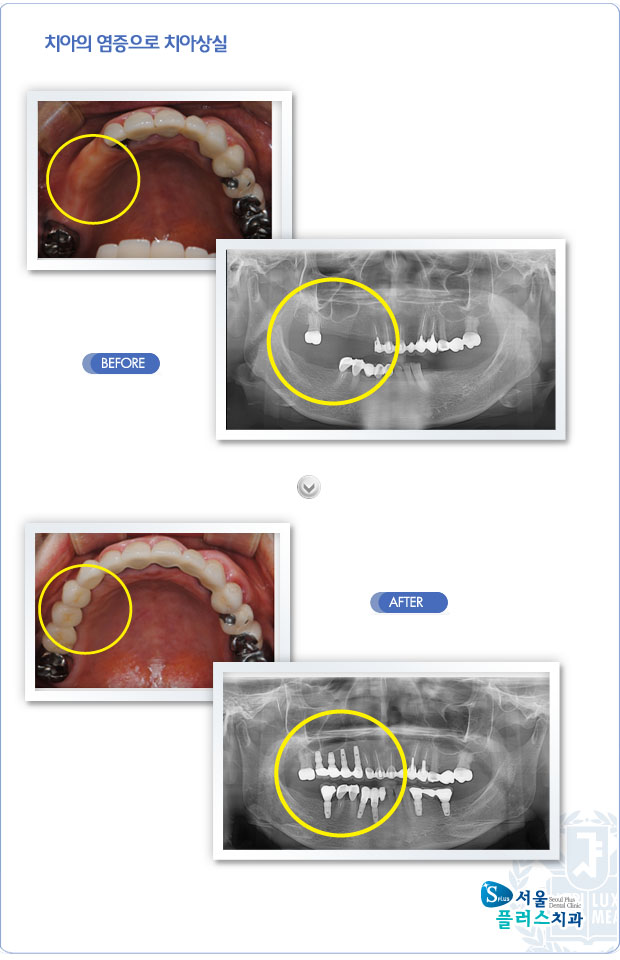

[임플란트] 치아의 염증으로 치아상실